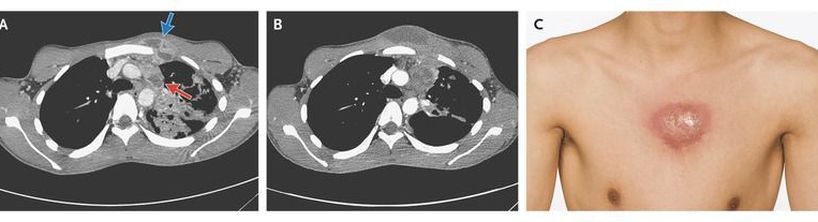

A previously healthy 18-year-old man was admitted to the hospital with a 3-month history of coughing, expectoration of reddish sputum, weight loss, and fever; a small region of swelling had developed on his anterior chest wall in the preceding week. A computed tomographic (CT) scan of the chest obtained on admission showed a collar-button abscess (a subcutaneous abscess connected to a deeper abscess by a passage), consisting of an abscess in a lymph node in the left mediastinum (Panel A, red arrow) connected to a subcutaneous abscess in the anterior chest wall (Panel A, blue arrow). CT also revealed an extensive parenchymal abnormality in the left upper lobe. A sputum smear showed acid-fast bacteria, and a culture grew pansusceptible Mycobacterium tuberculosis. Tests for human immunodeficiency virus were negative. The patient received 8 weeks of standard antituberculous treatment, but the infection progressed, with increased swelling, erythema, and fluctuation of the subcutaneous abscess (Panels B and C). The abscess was subsequently treated with open drainage. Pharmacologic treatment of a tuberculous abscess is seldom sufficient, and open drainage or surgical excision is often required. The patient has been without signs of relapse since surgery but required plastic surgery to improve the cosmetic result after drainage.